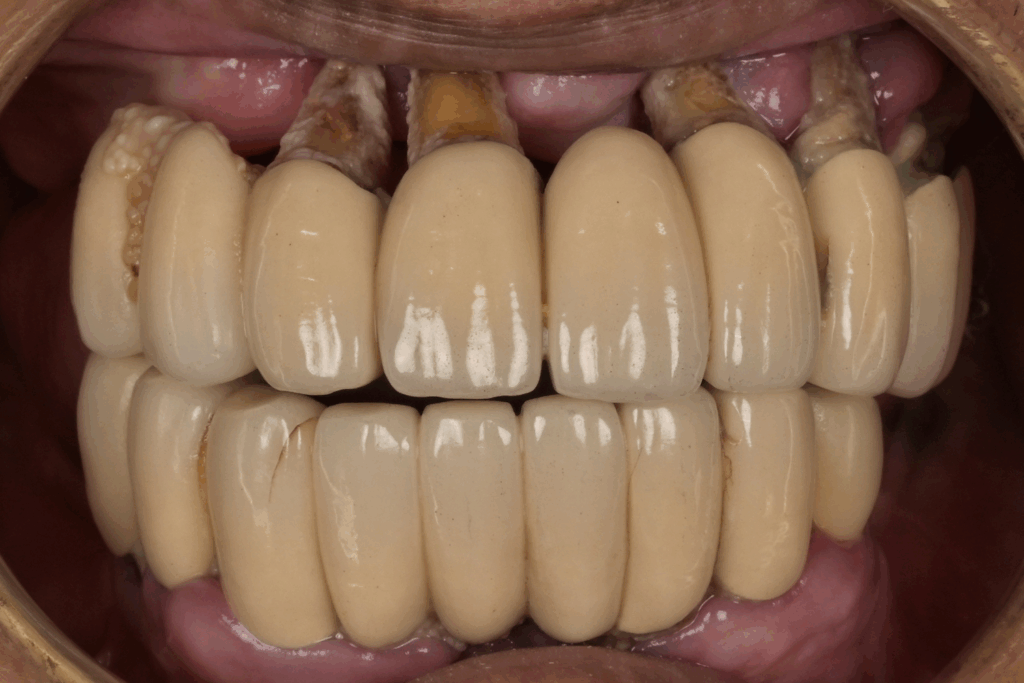

案例1. 上顎+下顎All on X

Before

After